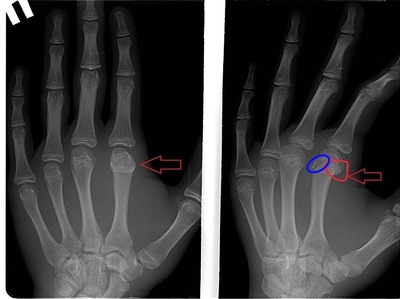

Насколько я поняла - вот трещина, красной линией, напоминающей круг, выделила.

Иллюстрация к комментарию

То что вы обвели красным кружочком это зона роста:) если присмотритесь подобные линии просветления есть и на остальных пястных костях

Для вашего удобства обвёл линию перелома синим, видно дефект кортикального слоя